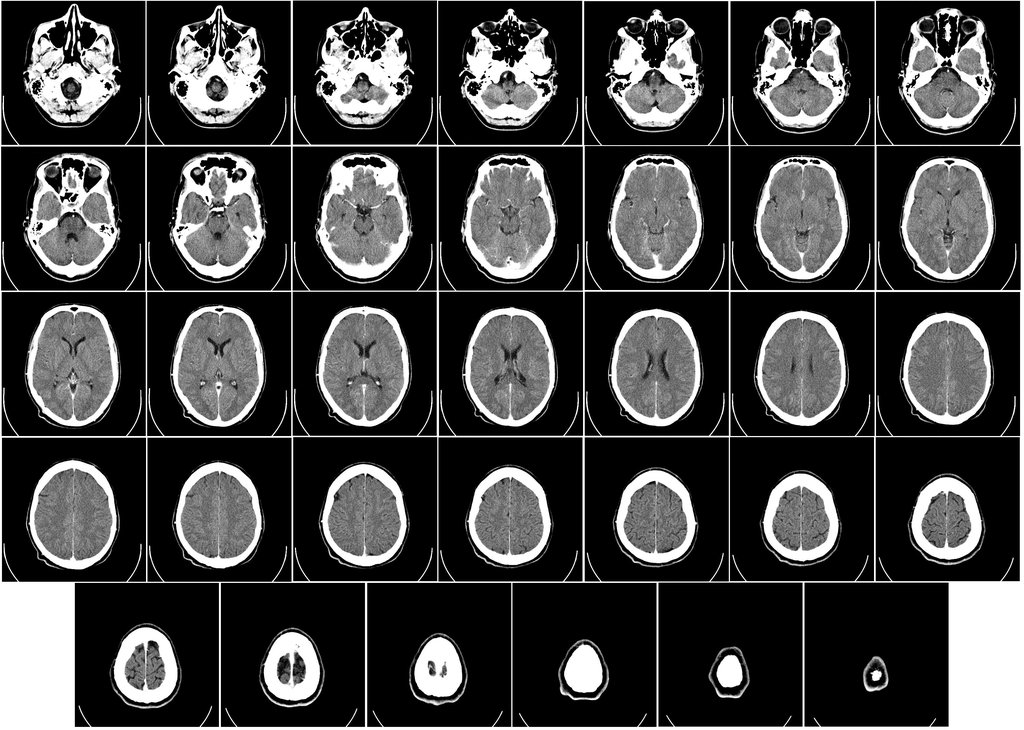

CT scan brain

A CT scan can generate images not just of bones and metal, but soft tissues. Here, the skull and the brain are visualized with equal accuracy. Wikimedia Commons

Perhaps the most important development came in the 1970s, with the first X-ray computed tomography machine, or CT scan. Using sensors to detect the output of X-rays beamed through the patient’s body, the machine creates elaborate images of bones, organs, and soft tissue all at once. Because each substance in the body is penetrated by the beam to a different degree, the machine can successfully distinguish between an arm and a spleen, and carefully recreate an impression of both. “That’s the most modern application of X-ray technology,” Banerjee says.